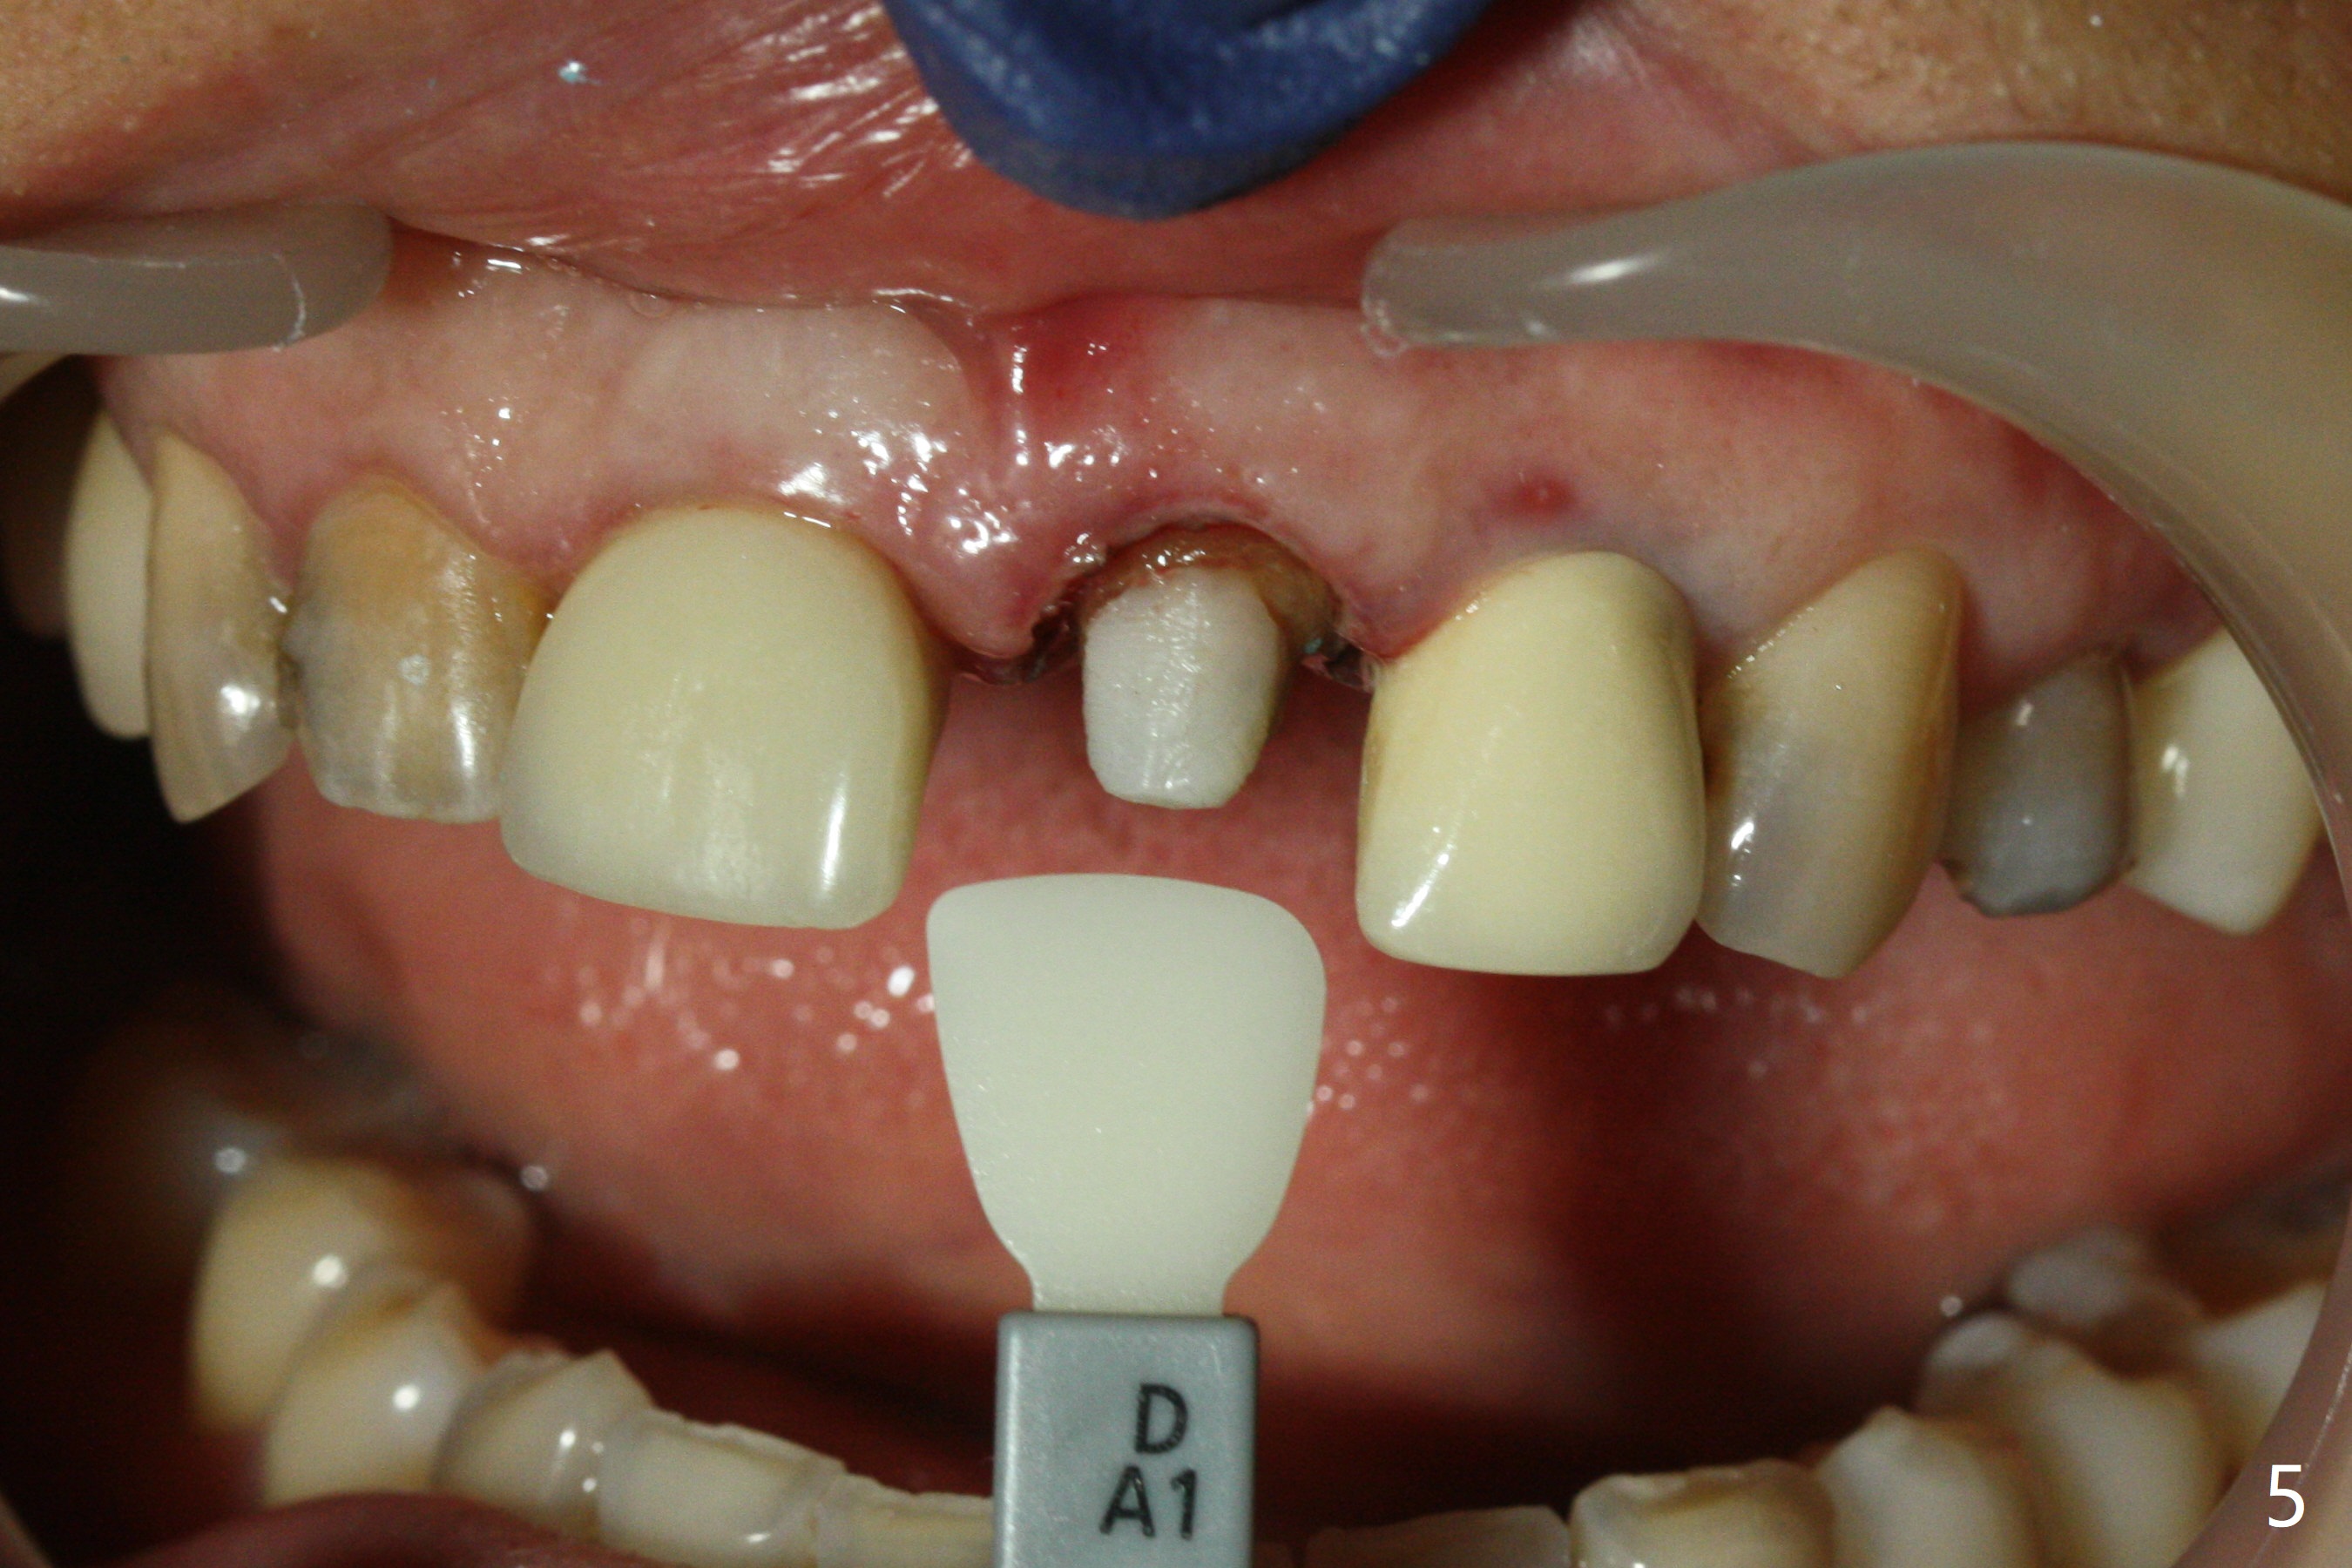

When the 44-year-old woman returns, the crown dislodges from #9 with palatal porcelain chip (Fig.1). Although the post is in place as compared to its dislodgement last visit, it is short and pointed (Fig.2,3 P). Because of the anterior deep bite (Fig.4), an implant restoration may not provide advantage; a new build-up is fabricated (B-U) for a new crown (Fig.5-6). The existing crown is reinserted for shade comparison (Fig.7 C). The gingiva at #8 and 9 is healthy, whereas that at #10 is not (Fig.8). PA taken 5 months later shows that the crown at #10 looks normal (Fig.9).